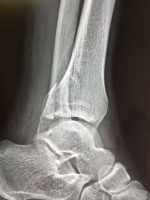

一例踝關(guān)節(jié)骨折的治療 關(guān)鍵疾病:左踝關(guān)節(jié)骨折(旋后內(nèi)收) 現(xiàn)病史【一般資料】 女性,28歲,農(nóng)民 【主訴】 摔傷后左踝部腫脹疼痛活動(dòng)受限2小時(shí) 【現(xiàn)病史】患者于2小時(shí)前干活時(shí)不慎從高處摔傷,左足著地,傷后即出現(xiàn)左踝部腫脹疼痛,不能站立行走,當(dāng)時(shí)無(wú)頭疼頭暈,無(wú)惡心嘔吐,急***就診,急診拍片示左踝關(guān)節(jié)骨折,后以“左踝關(guān)節(jié)骨折”收入我病區(qū)。 【既往史】既往體健,否認(rèn)高血壓病、糖尿病、冠心病等病史;否認(rèn)肝炎、結(jié)核等傳染病史;否認(rèn)手術(shù)史和輸血史,否認(rèn)食物、藥物過(guò)敏史,預(yù)防接種史不詳。 【個(gè)人史】 生于原籍,無(wú)外地久居史,無(wú)疫區(qū)接觸史,煙酒少量,24歲結(jié)婚,婚后育...